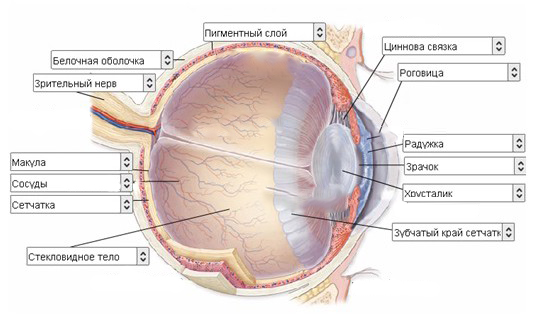

КТ-графики и изображение строения глаза